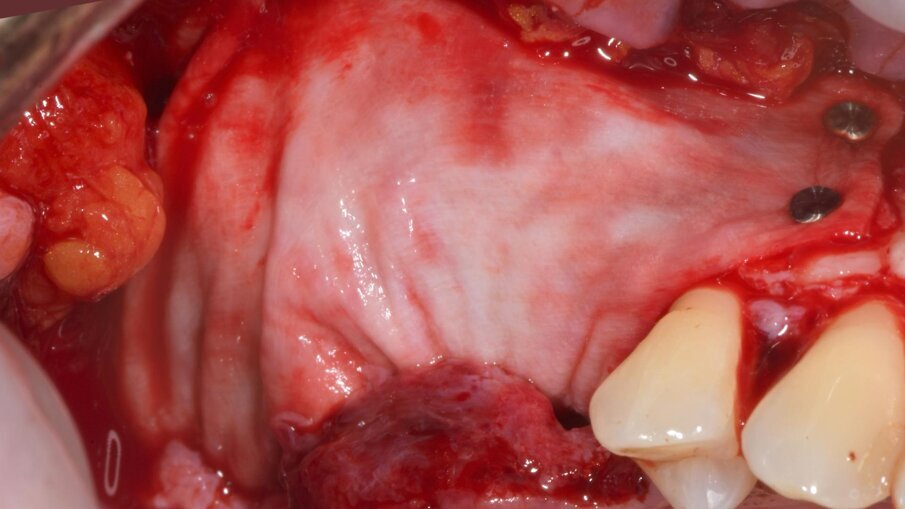

Dopo 9 mesi, è stata eseguita una seconda CBCT per valutare il volume di osso rigenerato e per pianificare la chirugia computer guidata (Fig. 23); i file .STL ottenuti dalla scansione 3D e i files .DICOM della CBCT sono stati utilizzati per pianificare l’inserimento degli impianti tramite una chirurgia computer guidata (Navimax, Biomax) (Fig. 24) . Il giorno della chirurgia implantare (T1), è stata eseguita un’incisione orizzontale para-crestale, per permettere l’esposizione della griglia e la sua rimozione, previa rimozione delle viti in titanio e dell’osso formatosi al di sopra di essa (Figg. 25, 26). L’esame clinico ha evidenziato una completa rigenerazione ossea del difetto osseo verticale, con assenza di pseudo-periostio o pseudo-periostio minore di 1 mm, di conseguenza pseudo-periostio di “classe 1” secondo la classificazione di Cucchi et al.20 (Figg. 27, 28). Successivamente, la dima chirurgica è stata posizionata e fissata nella posizione pianificata; i siti implantari sono stati preparati con frese progressive dedicate; e tre impianti conici (T3, Zimvie) sono stati inseriti nelle posizioni #15, #16 e #17, secondo la pianificazione protesicamente guidata eseguita precedentemente mediante il software da chirurgia guidata (Figg. 29-31). Gli impianti sono stati “sommersi”, attendendo la corretta osteointegrazione, ed è stata eseguita una chiusura per prima intenzione (Fig. 32). Dopo il posizionamento degli impianti, è stata eseguita una radiografia OPT (Fig. 33).